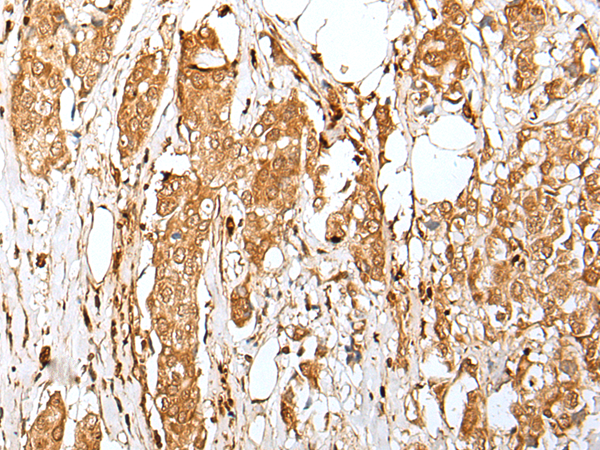

IHC positive control: |

Human tonsil and human breast cancer |